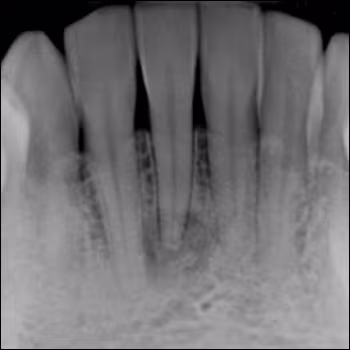

Periapical Lesion Involving a Mandibular Incisor Tooth

A 43-year-old African American female presents with a periapical lesion involving a mandibular incisor tooth.